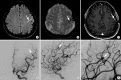

Intracranial hemorrhage is common and is caused by diverse pathology, including trauma, hypertension, cerebral amyloid angiopathy, hemorrhagic conversion of ischemic infarction, cerebral aneurysms, cerebral arteriovenous malformations, dural arteriovenous fistula, vasculitis, and venous sinus thrombosis, among other causes. Neuroimaging is essential for the treating physician to identify the cause of hemorrhage and to understand the location and severity of hemorrhage, the risk of impending cerebral injury, and to guide often emergent patient treatment. We review CT and MRI evaluation of intracranial hemorrhage with the goal of providing a broad overview of the diverse causes and varied appearances of intracranial hemorrhage.